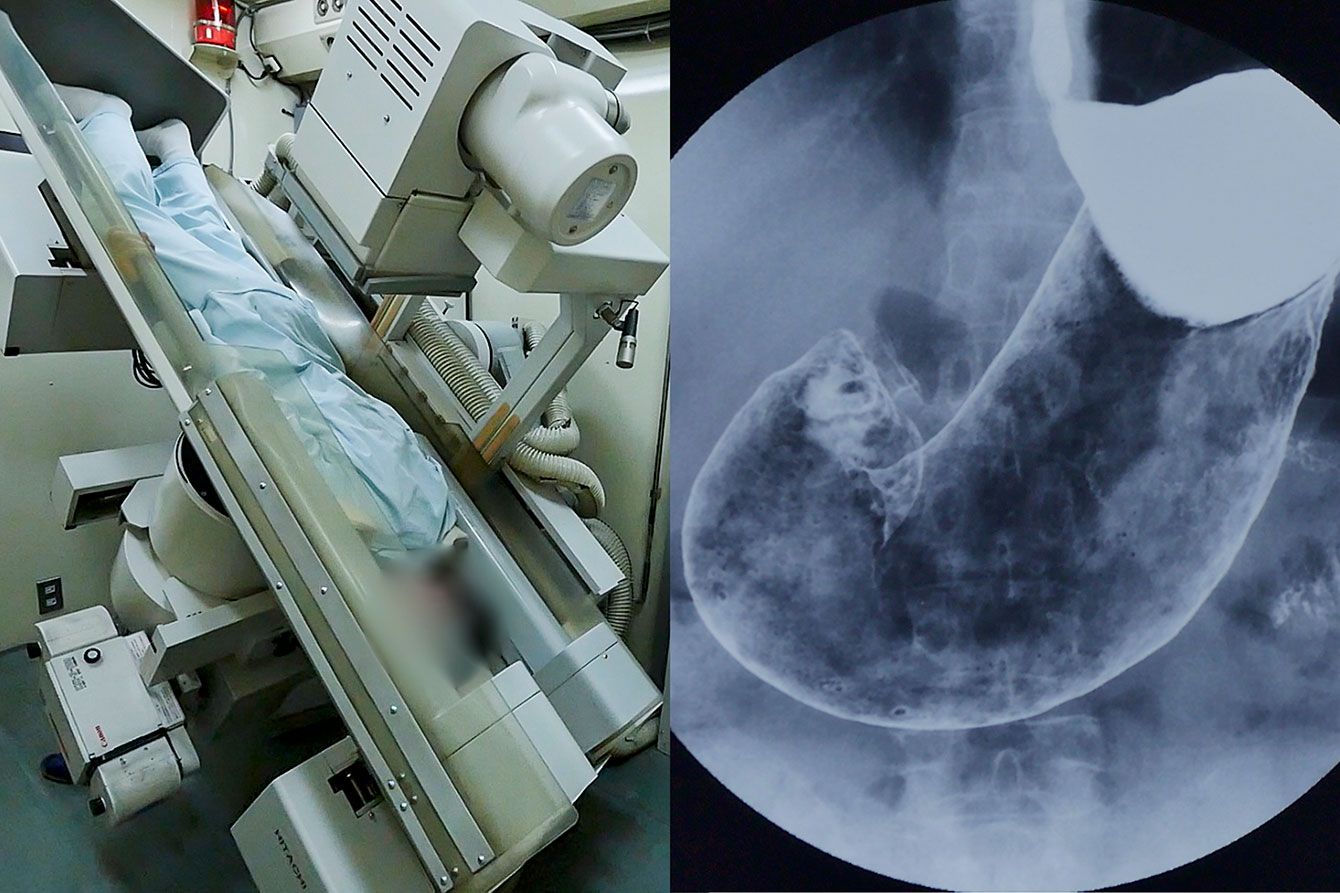

バリウムが原因で腸が破れた…胃がん検診の翌日に「緊急手術で人工肛門」となった61歳男性の怒りと後悔

胃がんバリウム検査の撮影場面

※写真はイメージです